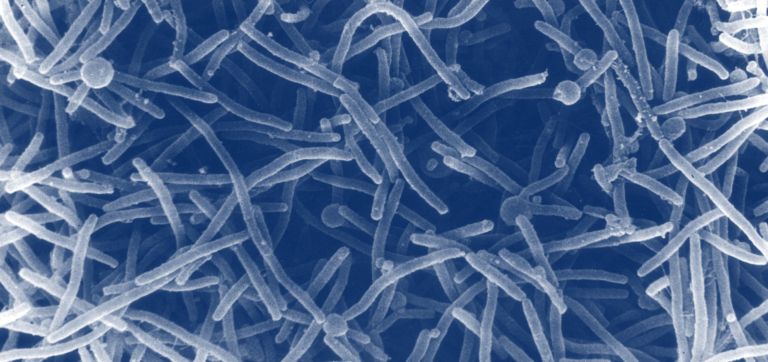

The most common treatments for BV are metronidazole or clindamycin antibiotics, which can be taken orally or vaginally.4 These treatments have been shown to reduce harmful bacteria in the vagina. However, Dr. Ravel notes that they do nothing to rebuild a strong and resilient VMB post-infection. He adds that antibiotics that broadly target all microbes may also “decrease the overall abundance of microbes in the vagina, which can leave open a gap for new invaders to take advantage of.”

You can think of antibiotics like pesticides: They do a great job at clearing fields of harmful pests, but they also get rid of beneficial bugs, and they don’t do anything to enrich the soil itself. It’s not surprising, then, that studies demonstrate over 50% of women who take antibiotics for BV have a recurring infection within three to six months.10

Beyond allowing recurrent infections, some antibiotics can also make women more susceptible to a vaginal yeast infection, or vulvovaginal candidiasis (VVC).12

“There are cases where a woman may take an antibiotic for another issue, then a yeast infection follows,” Dr. Ravel says, noting that this can happen when antibiotics deplete the microbiome of protective bacteria and create an opportunity for new yeast to grow or existing yeast to multiply.

Dr. Ravel, who has conducted many vaginal microbiome surveys, says that “about 20% of women have naturally occurring Candida yeast in the vagina but are asymptomatic.”13 This means that roughly 1 in 5 women are unknowingly dependent on a protective bacteria in the VMB to keep their yeast at a low level. However, this delicate balance can easily become skewed when antibiotics come into the picture.